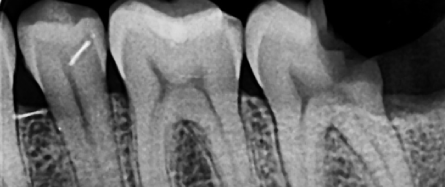

Clinical Examination

On examination, deep caries was noted on distal 37.

A periapical radiograph was taken, and treatment options were discussed. The patient agreed to undergo endodontic therapy for tooth 37.

Radiographic Examination :

Radiographs and clinical pictures during the treatment :

Master cone GP PA

Post-op xray.

Treatment Procedure and Radiographic Documentation

Radiographs and clinical pictures were taken during treatment, including:

• Master cone GP periapical radiograph

• Post-operative X-ray